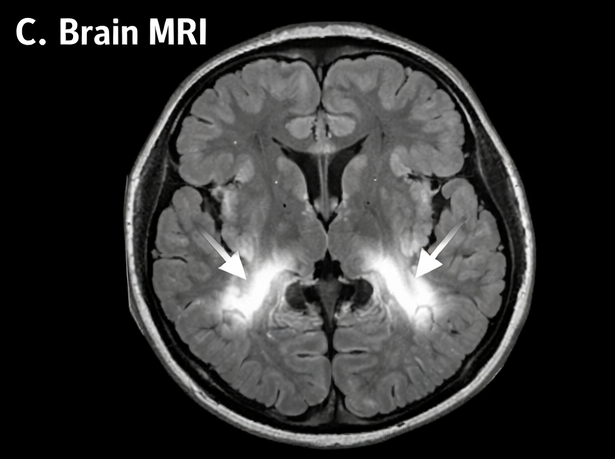

Magnetic resonance imaging (MRI) of the brain demonstrated diffuse cerebral edema with hyperintense signals in the brainstem and basal ganglia on T2-weighted and FLAIR sequences, suggestive of encephalitis.